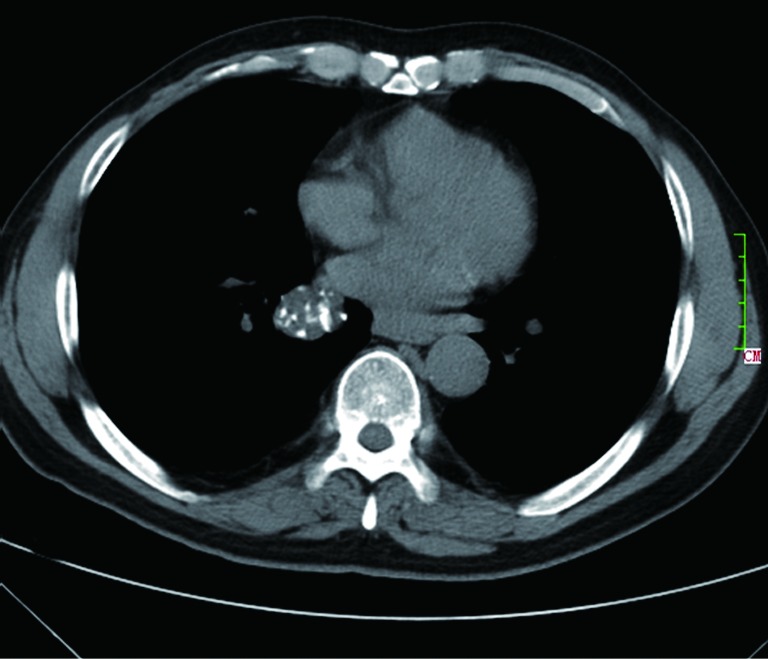

Figure 3.

CT shows a case of rounded atelectasis (arrow) with morphological features of subpleural location, curved course of blood vessels into the opacity, and evidence of pleural disease.